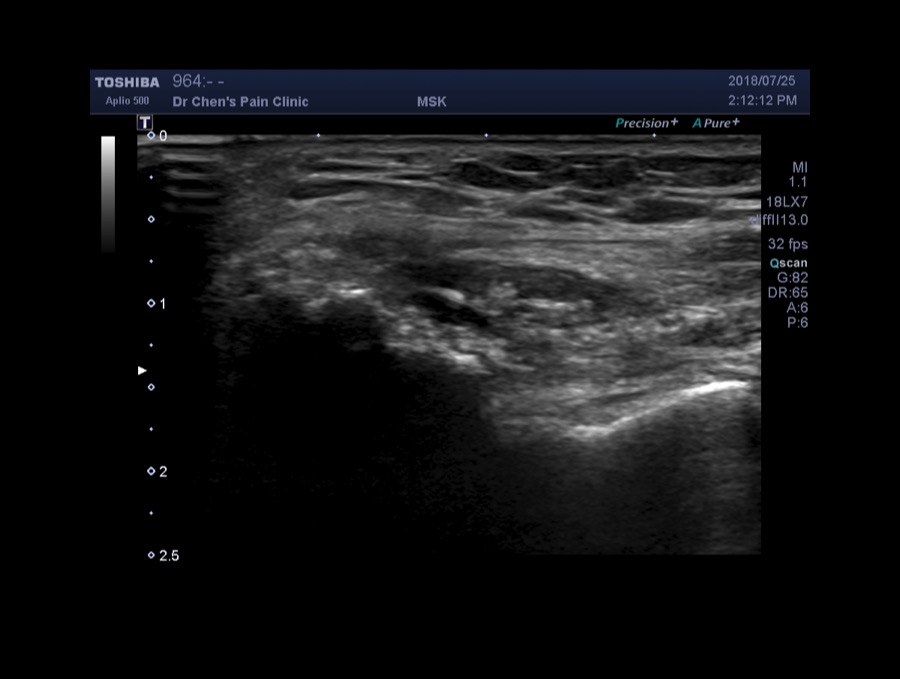

Pronator muscle tear

這是一個長期手肘內側疼痛的患者。(錄影)超音波檢查發現手肘內側肌肉裂傷